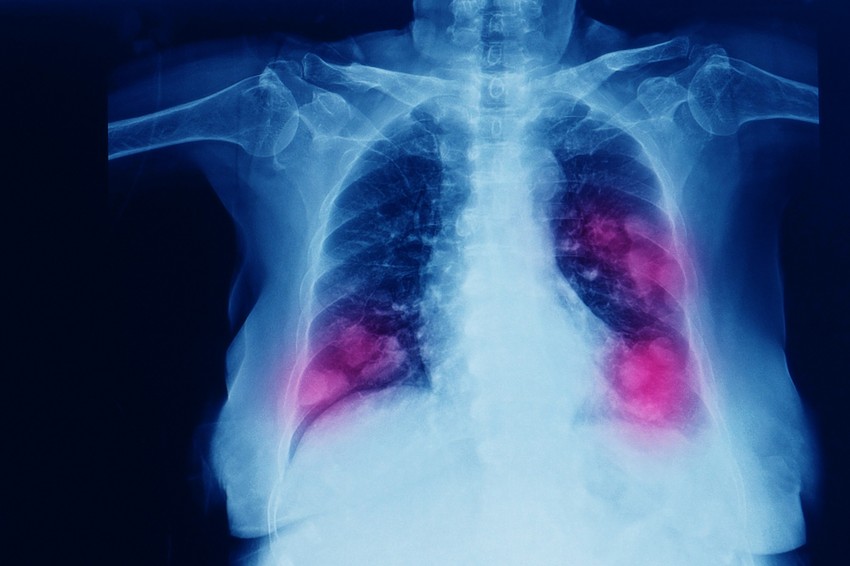

Egy idős beteg, akinek hagyományos módszerrel nem operálható tüdőproblémája volt, sikeres tüdőműtéten esett át a Jász-Nagykun-Szolnok Vármegyei Hetényi Géza Kórház-Rendelőintézetben.

A beteg jobb felső tüdőlebenyének daganatos eltávolítása volt a cél, bár tíz évvel korábban már hasonló műtétet hajtottak végre a bal felső lebenyén. A műtét során a nagyobb méretű jobb tüdő nem lélegzett, és csak a csonkolt bal tüdőn keresztül tudott a beteg levegőt venni.